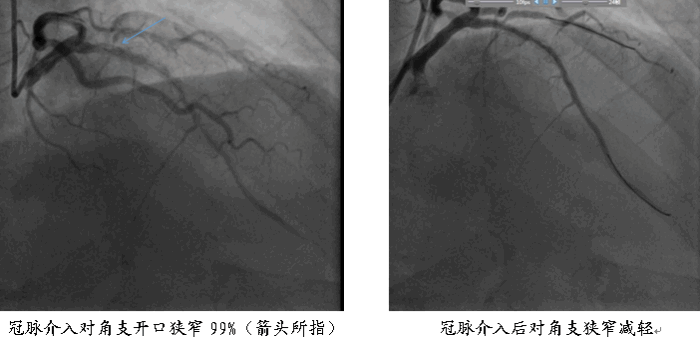

导管室已准备就位,周超飞副主任与金荣杰副主任医师,在田进文主任指导下展开冠脉造影:患者左冠第一对角支血管狭窄达99%,血栓堵塞严重,血流缓慢。在两位医生的精准操作下,引导导丝顺利通过血管,待血管预扩张后,采用药物球囊扩张技术进行精准疏通,当血管血流恢复TI MI3级(冠状动脉造影中评估血流速度重要指标,TIMI3级:造影剂能完全,迅速充盈远端血管腔并快速清除,表示血流正常),患者心电图ST段回落至正常基线,患者王先生转危为安。